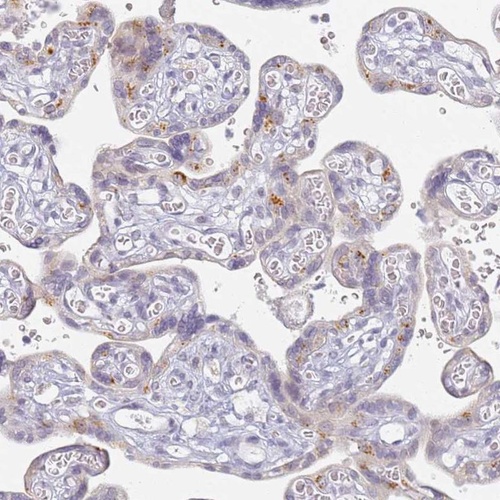

Immunohistochemical staining of human placenta shows strong granular cytoplasmic positivity in a subset of trophoblastic cells.